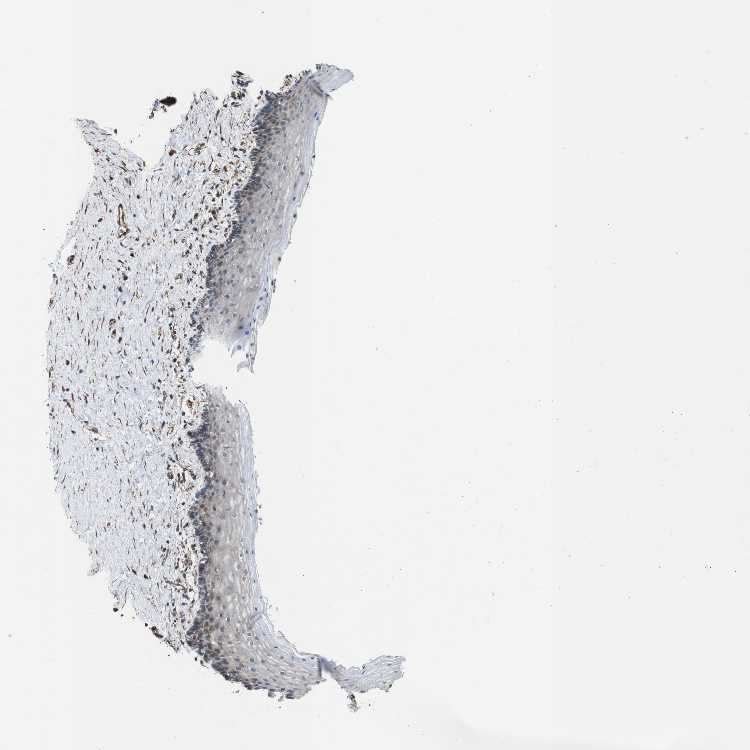

VAGINA - Antibody stainingi

Antibody staining in the annotated cell types in the current human tissue is reported as not detected, low, medium, or high, based on conventional immunohistochemistry profiling in selected tissues. This score is based on the combination of the staining intensity and fraction of stained cells.

Each image is clickable and will lead to virtual microscopy that enables deeper exploration of all samples and also displays staining intensity scores, fraction scores and subcellular localization as well as patient and tissue information for each sample.

Antibody HPA013321

Squamous epithelial cells Medium